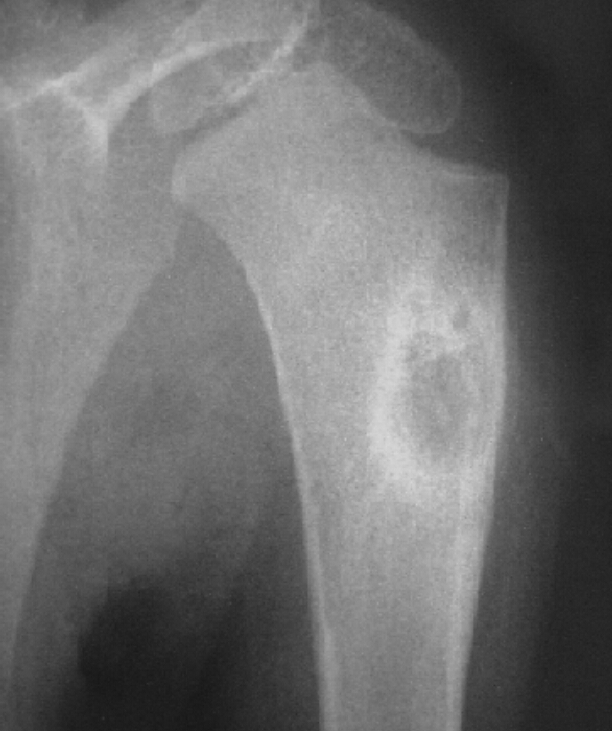

Findings? Diagnosis?

Geographic, eccentric, metaphyseal/epiphyseal, subarticular, soap bubble appearance, lytic, cortical thickening

Giant cell tumor